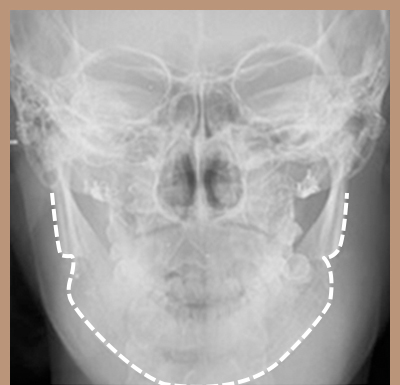

如果將我們的臉比作球,如圖所示,耳下方輪廓不是從正面看最寬的部位,而比最寬部位靠後。

因此除了耳下方輪廓外翻的少數情況,下頜角切除術不會縮小下頜寬度。

WIAD方下巴縮小術透過將皮質整體切除(full thickness corticectomy),實現最卓越的正面改善效果。

如果將我們的臉比作球,如圖所示,耳下方輪廓不是從正面看最寬的部位,而比最寬部位靠後。 因此除了耳下方輪廓外翻的少數情況,下頜角切除術不會縮小下頜寬度。 WIAD方下巴縮小術透過將皮質整體切除(full thickness corticectomy),實現最卓越的正面改善效果。

切除下頜角時,切除部位從正面看角度不夠明顯。

皮質切除術可以明顯縮小從正面看不見部位的線條。